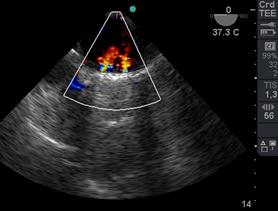

El reemplazo valvular puede corresponder a válvula mecánica (Figura 29) o biológica (Figura 30). Luego de CEC valoraremos la presencia de jets centrales normales y la ausencia de pérdidas periprotésicas, y medimos su gradiente medio.(45)

Figura 29 4 cámaras ME Doppler Color 2 jets leves, centrales y normales de regurgitación mitral luego de reemplazocon válvula mecánica. Imagen de VM mecánica bivalva.